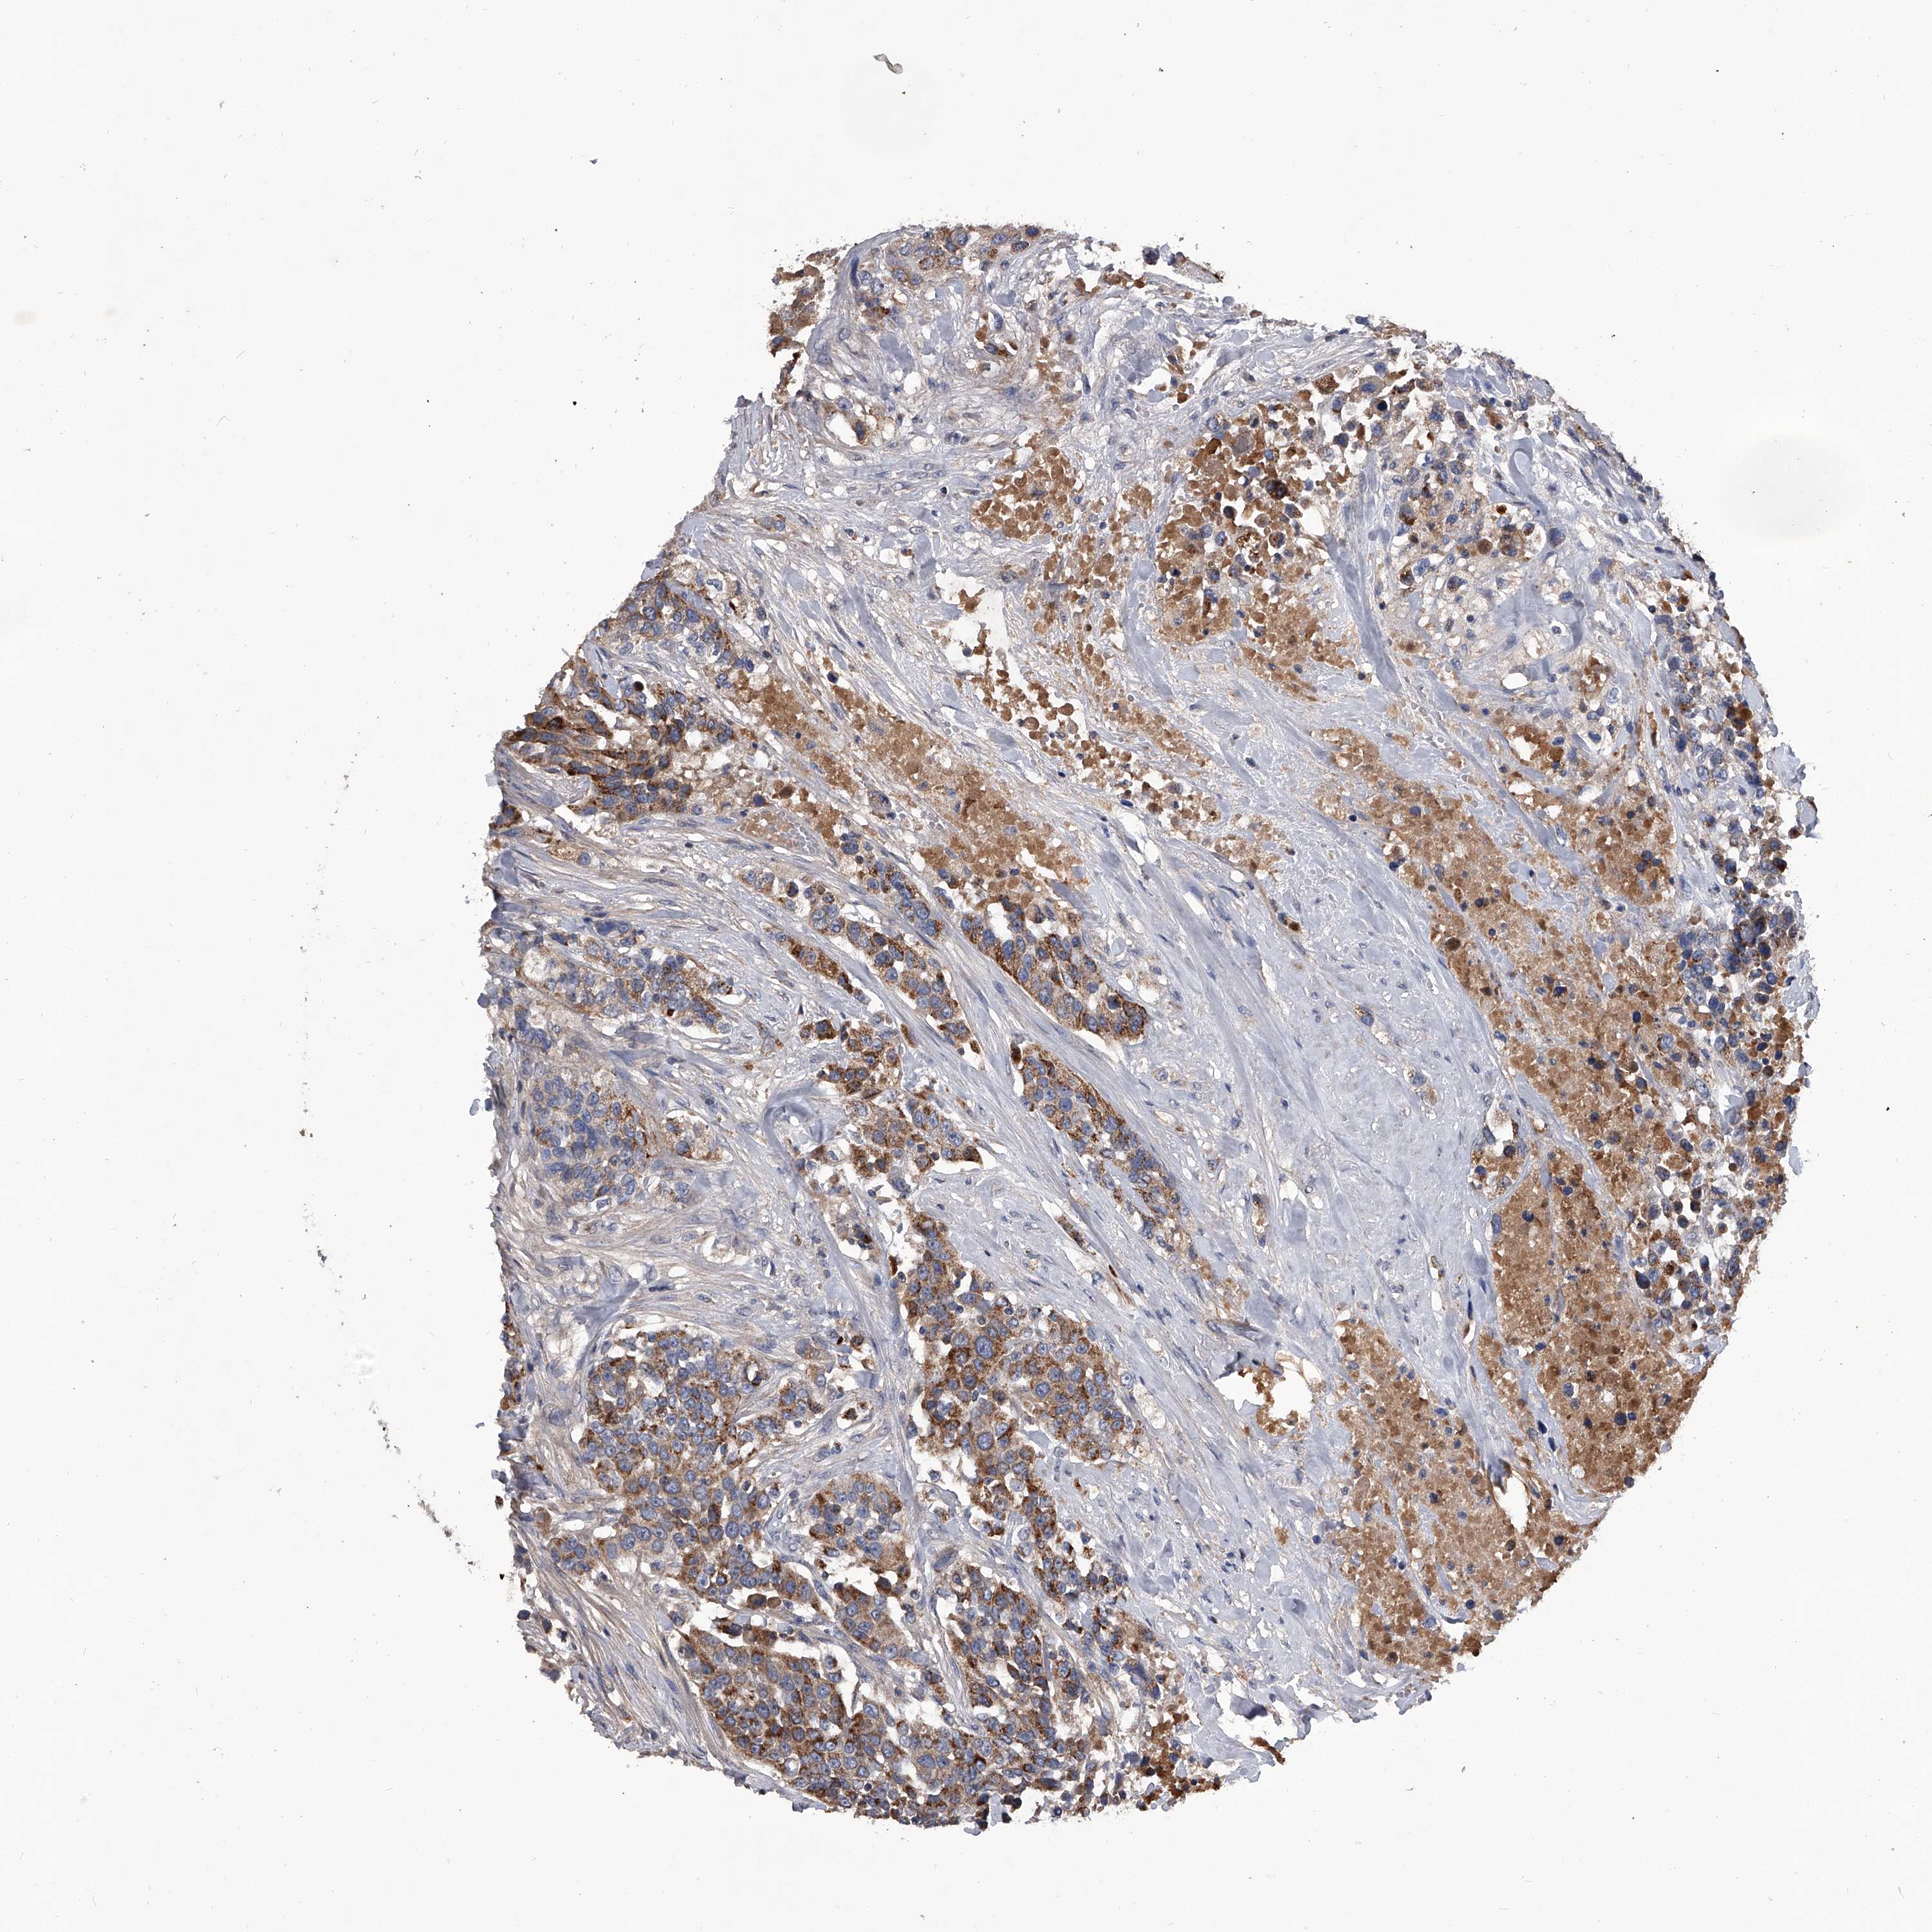

UROTHELIAL CANCER - Protein expressioni

A mouse-over function shows sample information and annotation data. Click on an image to view it in a full screen mode. Samples can be filtered based on level of antibody staining by selecting one or several of the following categories: high, medium, low and not detected. The assay and annotation is described here.

Antibody stainingi

Antibody staining in the annotated cell types in the current human tissue is reported as not detected, low, medium, or high, based on conventional immunohistochemistry profiling in selected tissues. This score is based on the combination of the staining intensity and fraction of stained cells.

Each image is clickable and will lead to virtual microscopy that enables deeper exploration of all samples and also displays staining intensity scores, fraction scores and subcellular localization as well as patient and tissue information for each sample.

Antibody HPA030278

Antibody CAB004511

Urothelial carcinoma, Low grade

Urothelial carcinoma, High grade